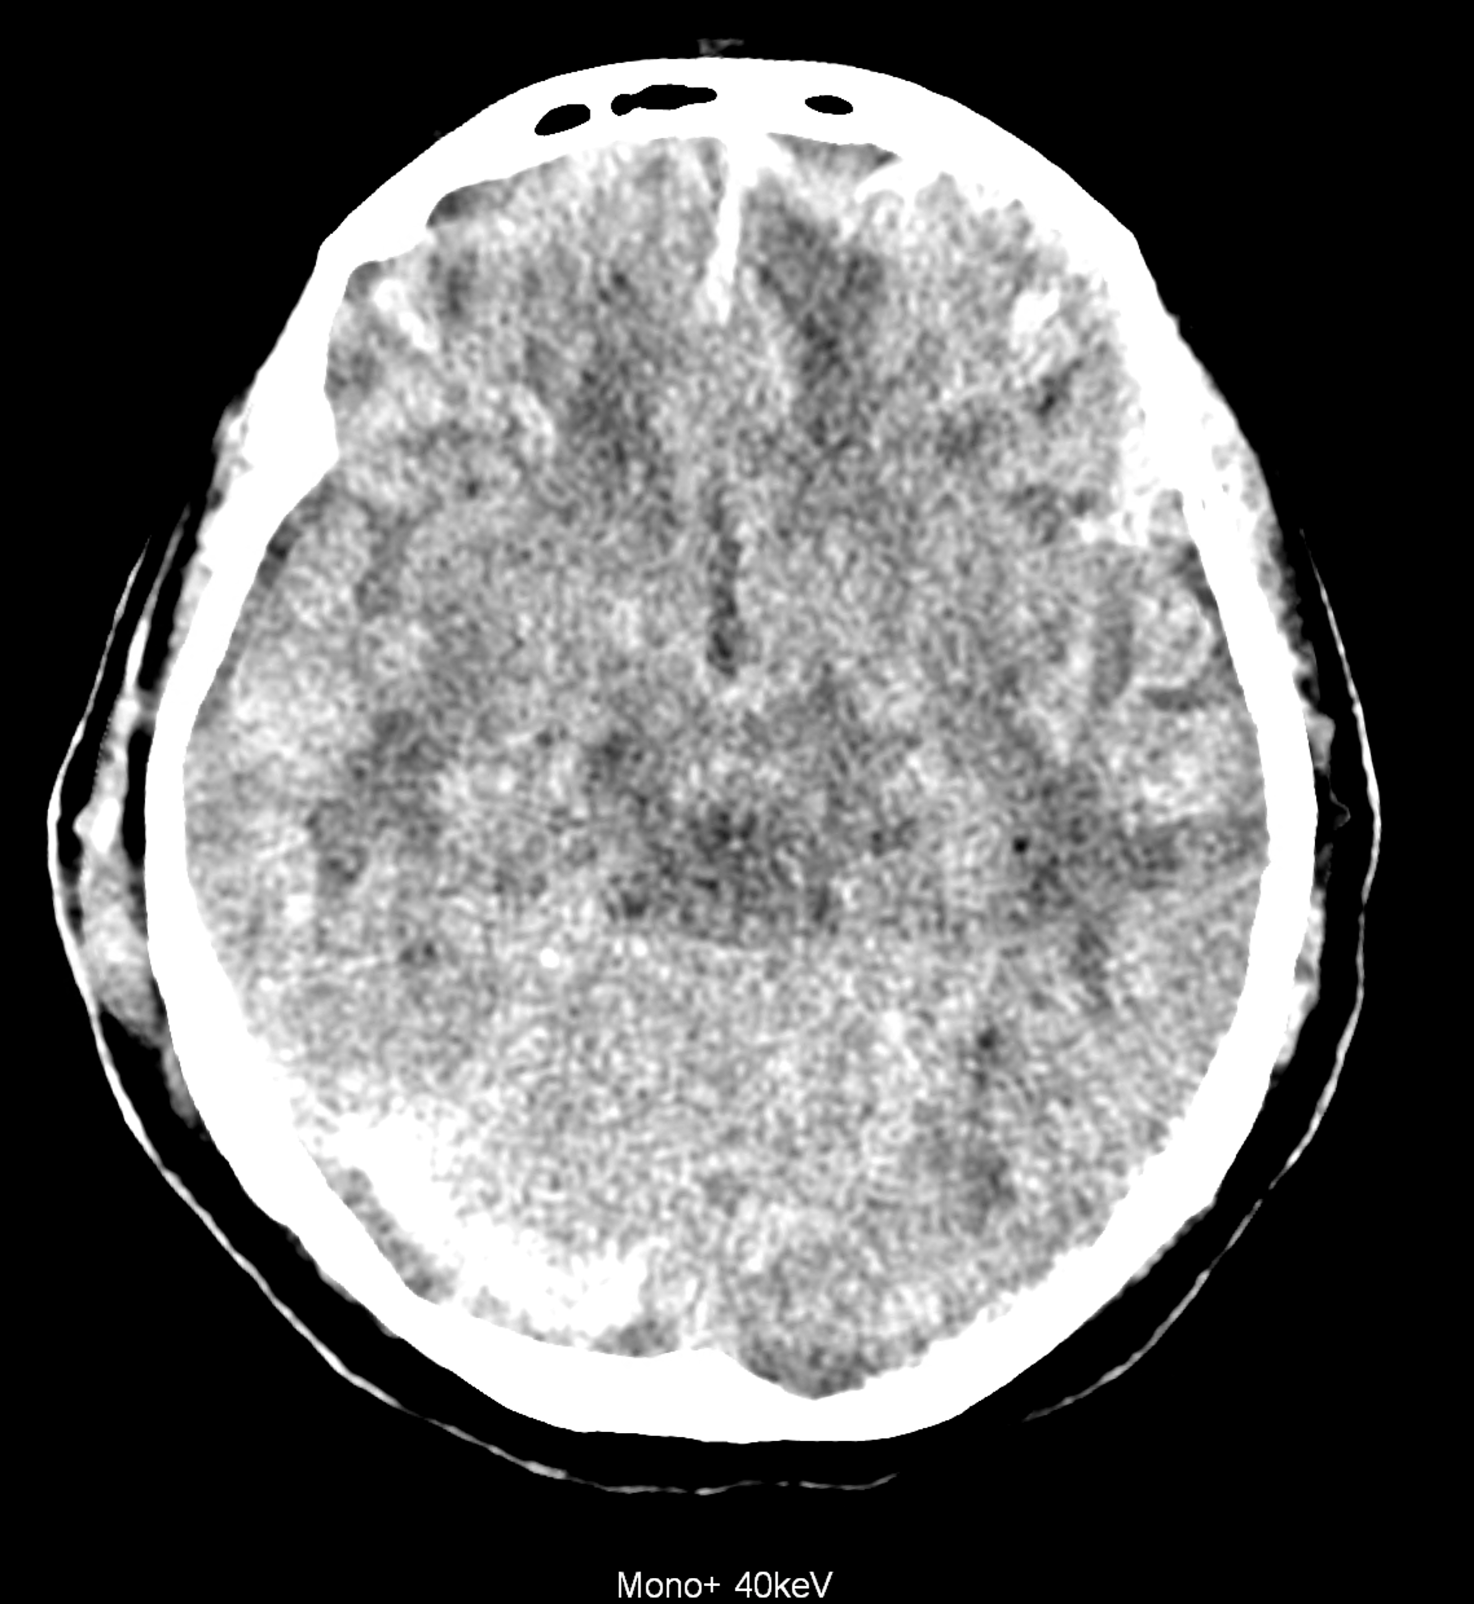

Bleeding is characterized by different absorption characteristics than healthy brain tissue (both gray and white matter) and cerebrospinal fluid. Due to the higher proportion of proteins with amino acids with disulfide bonds, the signal intensity increases at higher energies, making it possible to use monoenergetic imaging at energies above 140 keV, and/or virtual non-contrast. The hemorrhage then becomes more hyperdense, while the rest of the brain tissue acquires a uniform low signal. In addition to bleeding, areas of extracellular fluid of vasogenic origin are also imaged, i.e., in areas around contusion-type brain tissue injuries.

An example of the use of spectral imaging in complex brain injury, where contusions, diffuse axonal injury, subarachnoid hemorrhage, subdural hemorrhage, and blood in the ventricular system are present.

comparison of the images with the energies of monoenergetic reconstructions 40 keV, 67 keV (standard conventional reconstruction), 190 keV and virtual non contrast (VNC)